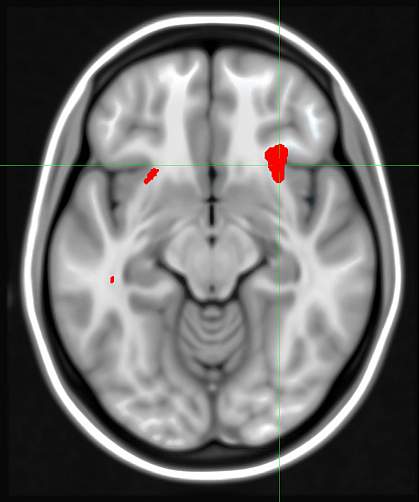

The researchers studied 63 adults, ages 18 to 60, with major depression. Participants underwent a brain scan using positron emission tomography (PET). A small amount of radioactively labeled glucose was used to reveal levels of glucose metabolism — a sign of brain activity — in different areas of the brain. Participants then completed 12 weeks of treatment with cognitive behavior therapy or the drug escitalopram.

Activity in a number of brain regions corresponded to treatment outcomes. The strongest correlation was in an area known as the anterior insula. Increased glucose metabolism in this area corresponded to successful treatment with medication but poor response to behavior therapy. Conversely, decreased glucose metabolism in the area was associated with success using behavior therapy but not escitalopram. One limitation of this potential imaging biomarker, the researchers note, is that it may not predict when neither of these therapies would work.